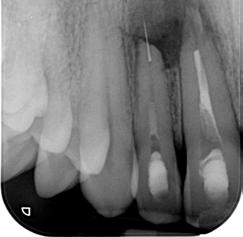

Patient said that these teeth were tender upon biting and chewing on them for the past couple of days in March 2022. He found a dentist in Perth and they started the initial stage of the root canal treatment for him. On examination, tooth 11 had a mesioincisal tooth colored restoration with good quality, while the 12 did not have any restorations. Periapical view showed that tooth 11 had root filling whereas there was no sign of root filling material in the 12. However, there was a broken instrument inside the apical third of the root. The broken part was extruded almost 4mm from the radiographic apex of the 12.

Radiograph 1

1. Pre-operative (16/01/2023)